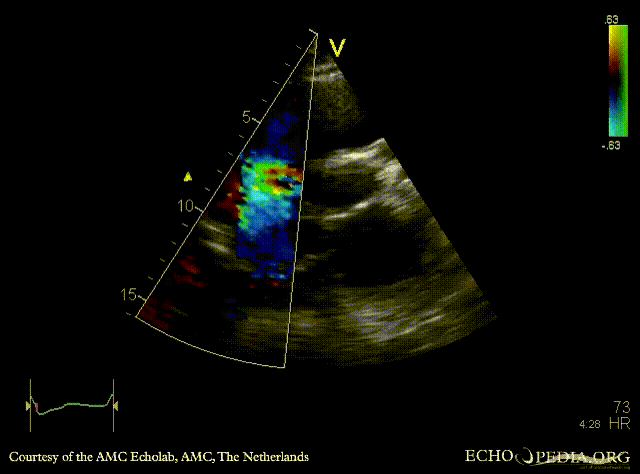

PSAX with Color Doppler: severe tricuspid regurgitation